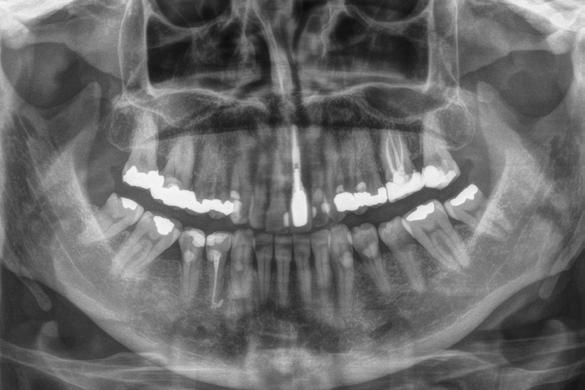

Figuras 1 y 2. Imágenes iniciales de la paciente. Se observa el diente en posición 21 con un cambio de color evidente y supuración espontánea a través del surco gingival. Asimismo, se aprecia el impacto estético del cambio cromático en la sonrisa y en el aspecto del frente anterosuperior.

Figura 3. Radiografía de la zona que muestra el tratamiento previo de apiconformación realizado en el incisivo para lograr el cierre apical, actualmente fracasado. Se observa además una lesión quística asociada al ápice.

Se presenta el caso de una paciente femenina de 47 años de edad al inicio del tratamiento, quien acude a consulta por dolor y supuración en el incisivo central superior izquierdo. En las imágenes iniciales se observa un diente con un cambio de color llamativo y una supuración espontánea a través del surco gingival (Figura 1). Esta alteración cromática, además de reflejar un problema asociado al diente, afecta de manera significativa la estética del frente anterior, como se aprecia en la imagen de sonrisa (Figura 2).

se realizó un tratamiento de apiconformación que, al momento de la revisión, mostraba signos de fracaso, con evidencia de infección y clínica sugestiva de fractura radicular (Figura 3).

Estos hallazgos confirman el éxito del procedimiento quirúrgico y de la posterior carga progresiva, con un mantenimiento óptimo de los tejidos duros y blandos a lo largo de más de dos décadas (Figura 15). Los cambios entre el momento inicial y el final del tratamiento son evidentes, especialmente al comparar la imagen intraoral de la primera visita con la tomada a los 22 años, donde la mucosa que rodea al diente 21 —y posteriormente al implante— se muestra engrosada, en buen estado de salud y con una estética destacable. Asimismo, la comparación entre la radiografía inicial, que evidenciaba el fracaso del tratamiento de conductos del diente en posición 21, y la radiografía a los 22 años, que muestra el implante sin pérdidas óseas asociadas, resulta elocuente (Figuras 16 a 19).

Figuras 16 y 17. Comparación entre la imagen inicial —diente con cambio de coloración, encía inflamada y pérdida de grosor— y la obtenida a los 22 años, que muestra estabilidad y salud gingival con el implante.